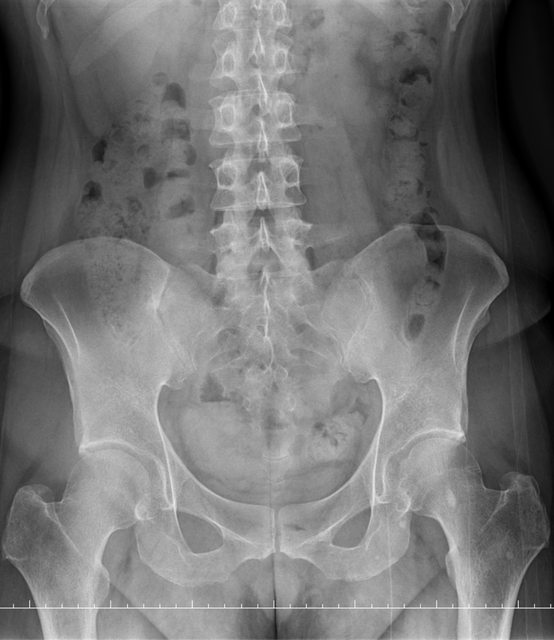

https://i.imgur.com/9HfkOHc.png

骨盆 https://i.imgur.com/h7KknkX.png

股骨頭放大特寫...左邊是右股骨 你覺得哪邊比較正常? https://i.imgur.com/16erxqZ.png

https://i.imgur.com/7NtJDKg.png

https://i.imgur.com/R4JFreK.jpg

醫生似乎很急 就問了二個問題就叫我去照X光 可能就一分鐘吧 回來看了下X光就說可能有神經壓迫 又是14天的消炎止痛藥 說還會痛再來回診或去看脊柱專科或復健科 感覺就是浪費了一天的時間排隊再排隊 沒得到答案 也沒有得到解決... 然後拿了吃越多可能洗腎越快的止痛藥 會不會下次脊柱專科也開14天消炎止痛說如果還有問題叫你去掛神經科? 為何不給我照MRI呢?我第一次去看問了MRI就還是只給我照X光 1.2期X光照了也不一定有異常,我實在不懂不用MRI的邏輯 體驗實在太差了,當然我也知道當有一百號排隊時問診就不可能細到哪怕只有15分 我想不等直接掛看看禮拜三神經科會怎解釋了 ※ 編輯: capybaradash (118.166.44.25 臺灣), 07/31/2023 14:29:17 ※ 編輯: capybaradash (118.166.44.25 臺灣), 07/31/2023 14:37:27

看了下治療方法,那有看等於沒看了 照MRI似乎也是白做,自費照根本浪費 其實X光以我外行人放大好幾倍看過去,左股骨跟大腿骨明顯狀態較差 不清楚醫生是不是有鷹眼,小小一張看過去就說沒什問題 我是不會去考慮手術的 小時候骨折都是看國術館 還減壓股頭打孔...開刀100%NO 治療方法 1.拐杖 2.藥物治療(1)非類固醇類消炎止痛藥(NSAID) (2)口服雙磷酸鹽類藥物 (3)血管擴張劑 (4)高壓氧 目前股骨頭缺血性壞死的治療,根據現有的證據,仍然以手術為主流。 於早期(第一、二期),尚未塌陷的股骨頭缺血性壞死,髖關節減壓手術值得一試, 至於第三、甚至第四期股骨頭缺血性壞死,人工髖關節置換術能夠有效的解除疼痛以及恢 復行走負重的功能。 ※ 編輯: capybaradash (118.166.44.25 臺灣), 07/31/2023 16:04:20

g17321732: 1.骨頭看起來沒大問題,x光不是放大找不一樣這麼簡單 07/31 18:18

g17321732: 3.MRI對你的幫助不大,X光已經足夠清楚,不用花冤枉錢 07/31 18:18

yasmine1030: 人體不是百分百對稱我實在看不出你X光兩邊股骨有何差 08/01 01:29

yasmine1030: 異 08/01 01:29